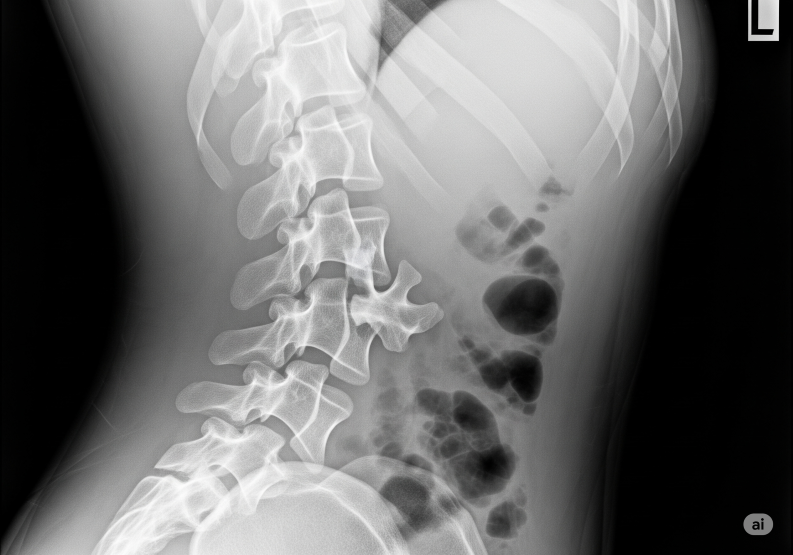

๐Ÿฉป ThoracoLumbar Extension Fracture (TLEF)

A TLEF is a spinal fracture occurring in the thoracolumbar junction (T10โ€“L2 region), usually due to extension injury (backward bending).

Itโ€™s one of the fracture patterns described in the AO Spine Classification System.

๐Ÿ”น Diagnosis

. X-ray of thoracolumbar spine.

. CT scan โ†’ to assess fracture pattern.

. MRI โ†’ to check for spinal cord/nerve injury and ligament damage.